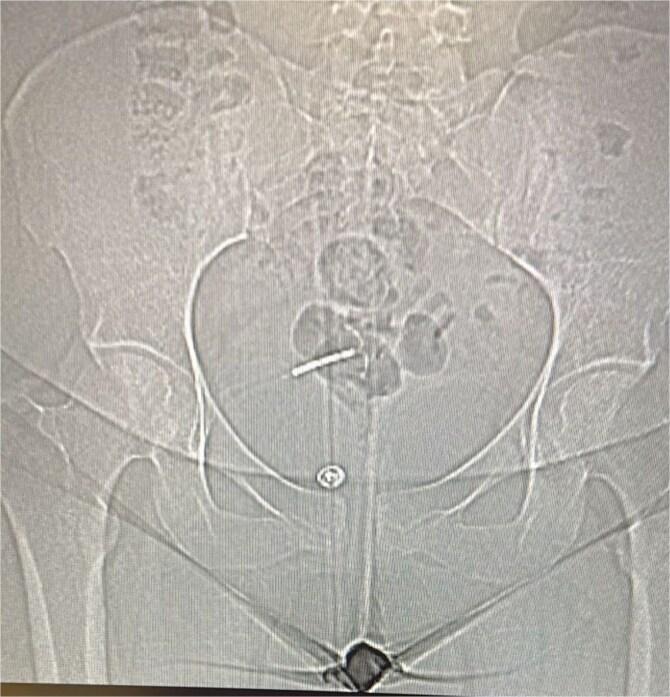

Intrauterine devices (IUDs) are a common and effective method of long-term contraception. However, rare complications such as uterine perforation and subsequent migration of the IUD to adjacent organs can occur. This case report describes a 29-year-old woman who presented with persistent abdominal pain and urinary symptoms secondary to IUD migration into the abdominal cavity, complicated by abscess formation. The case highlights the importance of considering IUD migration in patients with a history of IUD placement who present with abdominal or urinary complaints. It also underscores the need for routine post-insertion checks and thorough patient education to minimize risks.

宫内节育器(IUD)是一种常用且有效的长期避孕方法。然而,可能会发生诸如子宫穿孔以及随后IUD迁移至邻近器官等罕见并发症。本病例报告描述了一名29岁女性,她因IUD迁移至腹腔并伴有脓肿形成而出现持续性腹痛和泌尿系统症状。该病例强调了对于有IUD放置史且出现腹部或泌尿系统不适的患者,考虑IUD迁移的重要性。它还强调了进行常规放置后检查以及对患者进行全面教育以将风险降至最低的必要性。